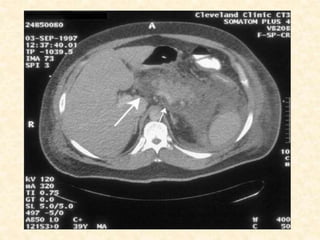

Computer Tomography (CT)

• Imaging modality of choice for diagnosis, determining

severity, and identifying complications

• Sensitivity: 90% for diagnosis of acute pancreatitis

• Specificity: 98-100%

• Not necessary for mild acute pancreatitis; however is

useful to rule out other abdominal processes presenting

with abdominal pain.

• Mild disease: no abnormalities, diffuse enlargement of

pancreas, loss of normally sharp border, homogenous

attenuation, inflammatory stranding in peripancreatic fat

and adjacent soft tissue, fluid collections, pseudocysts,

pancreatic necrosis

• Necrotizing pancreatitis:

Non-enhancement of ≥ 1/3 of pancreas or

>3cm of non-enhancement of the

pancreas on dynamic, IV contrast-

enhanced CT.

If > 30% gland involved, sensitivity

approaches 100%